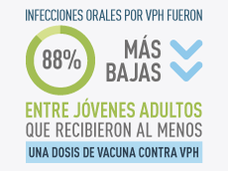

Vacunación contra el VPH relacionada con disminución de infecciones orales por VPH

Un estudio de más de 2600 jóvenes adultos encontró que la frecuencia de infección oral por cuatro tipos de VPH, incluyendo dos tipos que causan cáncer, fue 88 % más baja en quienes informaron haber recibido al menos una dosis de una vacuna contra el VPH que en quienes no estaban vacunados.